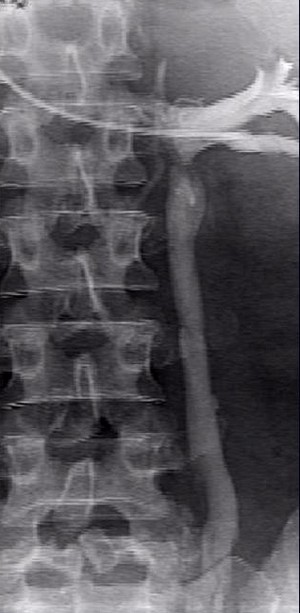

Примечательно, что абсолютно верную и точную информацию о наличии заболевания, состоянии вен малого таза на финальном этапе обследования помогает получить проведение инвазивного рентгеноконтрастного исследования. Во время селективной оварикографии и тазовой флебографии врачи уточняют анатомические особенности положения, строения яичниковых сосудов, их диаметр, выявляют количество и характер притоков гонадных сосудов, наличие рефлюкса, свойственного внутренним и яичниковым подвздошным венам, а также связь подкожных и сосудов малого таза.

Данная процедура предусматривает введение эмболизационных (закупоривающих) спиралей в вену через диагностический катетер, что позволяет полностью закупорить патологический кровоток. Операция не занимает много времени. При этом пациент может вернуться к привычной жизни уже в ближайшее время. Период реабилитации является несложным.